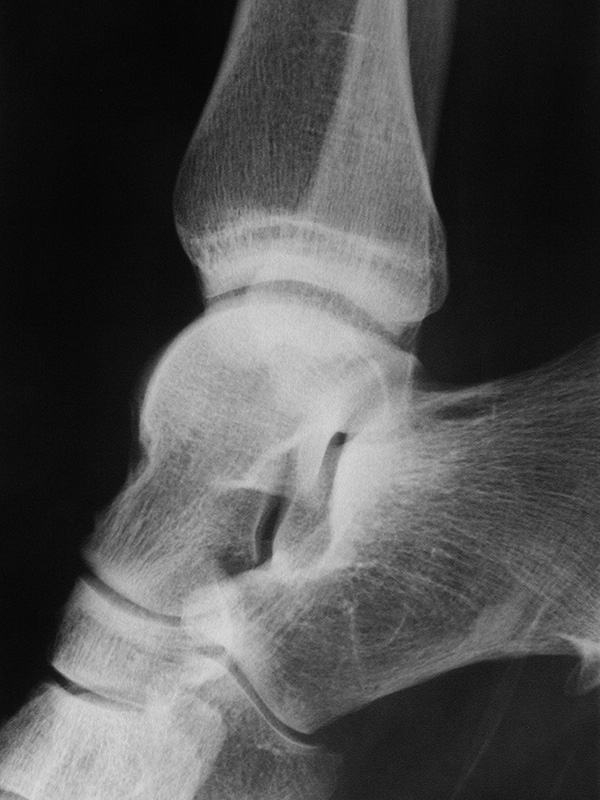

Sprunggelenk Mortise Aufnahme ohne Belastung (Mortise-View)

Kennzeichen des Röntgenbildes:

• Darstellung des Talusdoms ohne Überlagerung.

• Das Sprunggelenk befindet sich dabei in 90° Stellung, um eine Überlappung des Kalkaneus mit der distalen Fibula zu vermeiden.

• Der Weichteilmantel ist erkennbar.

Besondere Bemerkungen zum Beispielbild:

• Die Innenknöchelfraktur ist deutlich besser nachvollziehbar als bei der ap Aufnahme (siehe vorheriges Bild).

• Keine Stufe im Gelenk.

• Die Wachstumsfugen sind noch erkennbar, im Wesentlichen aber geschlossen.